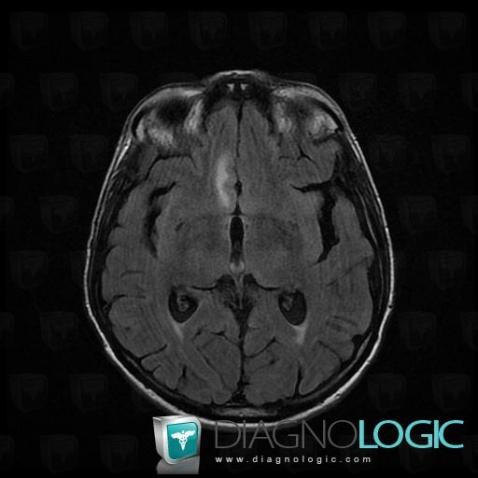

Les images ci-dessous illustrent ce dossier pour les diagnostics Carcinose méningée, Méningite carcinomateuse, pour les modalités (IRM)

Voici les informations spécifiques à l'image clé ci dessus:

- Diagnostic Méningite carcinomateuse, Localisation(s) Région cortico sous corticale, comportant les gammes Lésion corticale